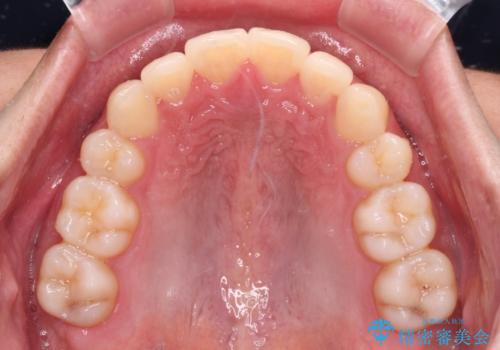

矯正治療の後戻りをインビザライン・ライトで解消

- 矯正治療の後戻りを気にして来院された患者様です。

後戻りは軽微であったので、インビザライン・ライトにより矯正治療を行うこととしました。

インビザライン・ライトは提供されるマウスピースの数に制限があり、通常のタイプよりもマウスピース提供期間が短くなっている一方、安価に治療を行うことができるプランです。

治療のゴールも変更できないため、軽微な歯列不正や、後戻り改善などに適しています。

矯正治療後は、再度後戻りすることを極力回避するために、下顎前歯の舌側を細いワイヤーを用いて保定することとしました。